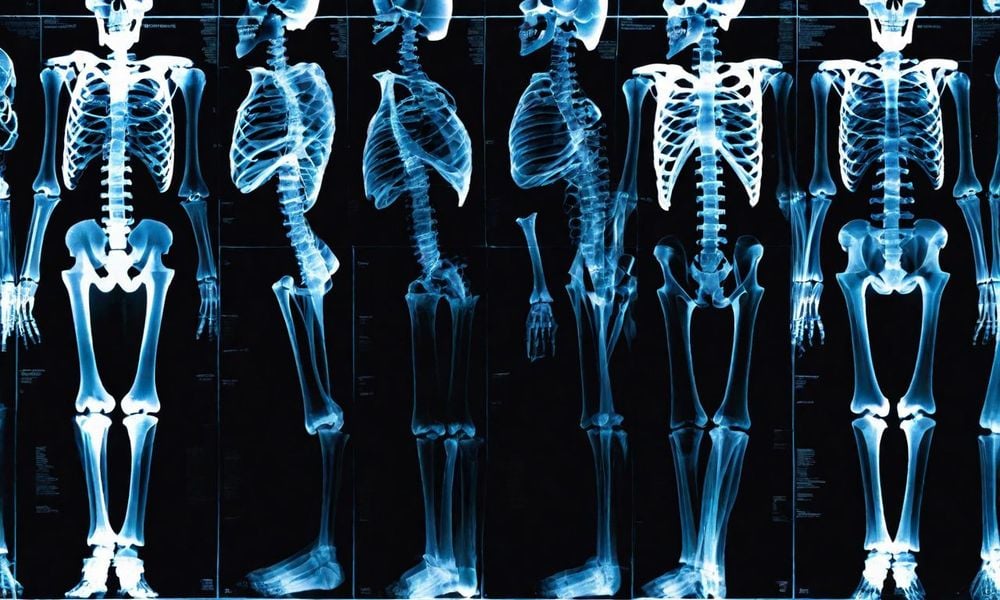

DEXA (Dual Energy X-ray Absorptiometry) là phương pháp đo mật độ xương phổ biến nhất thế giới. Phương pháp này sử dụng liều lượng tia X thấp hơn so với chụp X-quang phổi. Độ chính xác của DEXA cao, dao động từ 85% đến 99%.

Đây là kỹ thuật sử dụng tia X năng lượng kép giúp định lượng mất xương và theo dõi người đang điều trị. Phương pháp này thường được áp dụng ở cột sống, cổ xương đùi và có thể là xương toàn bộ cơ thể.

Đôi khi phương pháp DXA được thực hiện kiểm tra xương toàn bộ cơ thể.